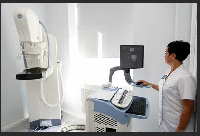

На рабочем месте производится обучение работе на Вашем оборудовании.

Любого доктора можно быстро подготовить как рентгенлаборанта и дать необходимые знания для оценки рентгенограмм.

Изучение проблемы низкого качества рентгенограмм на Вашем оборудовании.